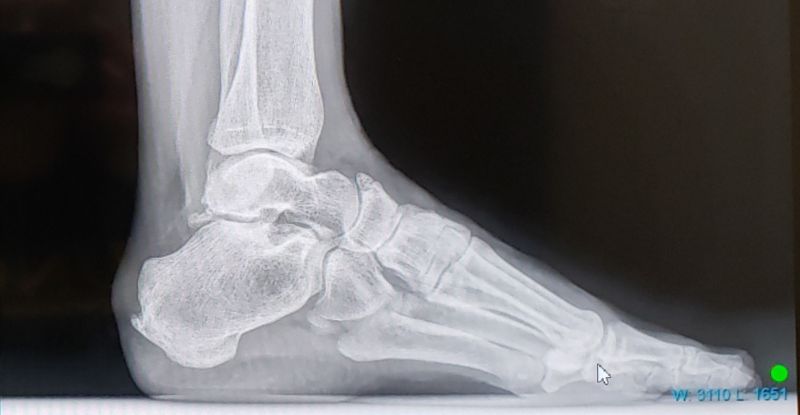

Because I LOVE x-rays, here’s two photos of the culprit. See that little hook on the back of my heel? Uh-huh. It sits right on my Achilles tendon.